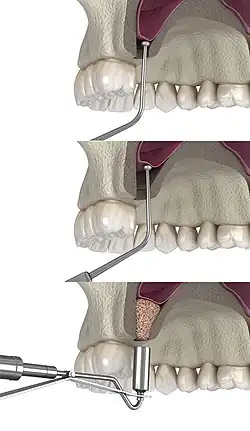

The procedure is performed intraorally, where the surgeon makes an incision into the gum. Once the incision is made, the surgeon then pulls back the gum tissue, exposing the lateral bony wall of the sinus. The surgeon then creates a "window" into the sinus, exposing the Schneiderian membrane. The membrane is separated from the bone, and bone graft material is placed into the newly created space. The gums are then sutured closed, and the graft is left to heal for 4 to 12 months.[8]

2) The soft tissue is flapped back to expose the underlying lateral wall of the left maxillary sinus.

3) The bone has been removed with a piezoelectric instrument, exposing the underlying Schneiderian membrane, which is the lining of the maxillary sinus cavity.

4) Through careful instrumentation, the membrane is peeled from the inner aspect of the sinus cavity.

5) The membrane has been reflected from the internal aspect of the inferior portion of the sinus cavity; one can now visualize the bony floor of the sinus cavity without its lining membrane (note the triangular ridge of bone within the sinus, known as an Underwood's septum).

6) The newly formed space within the bony cavity of the sinus, yet inferior to the intact membrane, is grafted with human cadaver allograft bone. The floor of the sinus will now be roughly 10mm or larger than before, providing enough room to place dental implants into the edentulous site.